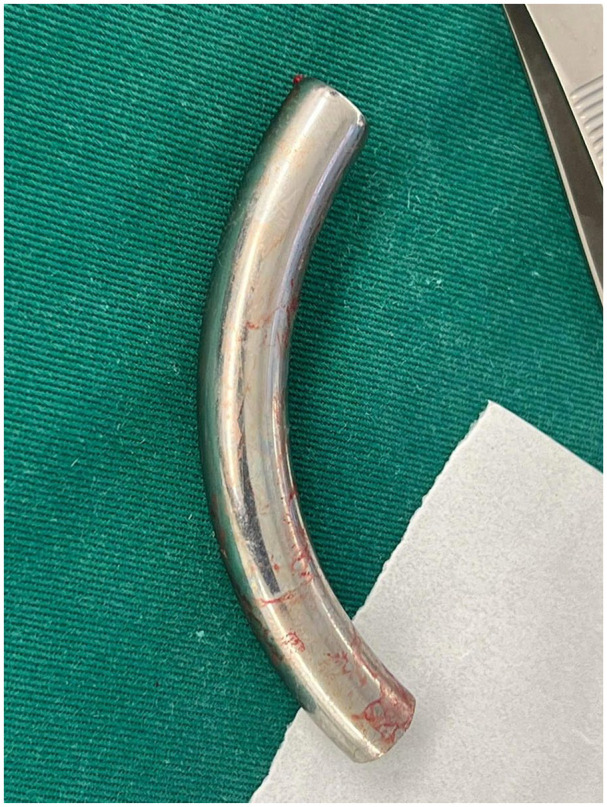

Case presentation: A 43-year-old male, with a tracheostomy tube in place for 8 years following a neck blast injury, presented with a foreign body in his airway. Chest X-ray revealed a fractured metallic tracheostomy tube lodged in the left main bronchus. The tube was successfully removed by rigid bronchoscopy under general anesthesia, and the patient was discharged in good condition with a new tracheostomy tube.

Discussion: Tracheostomy tubes, typically made of polyvinyl chloride or metal, can fracture due to prolonged use without regular check-ups, or replacement. Patients may present with mild respiratory symptoms or be asymptomatic. Diagnosis is confirmed by X-ray, and removal is performed via rigid bronchoscopy.